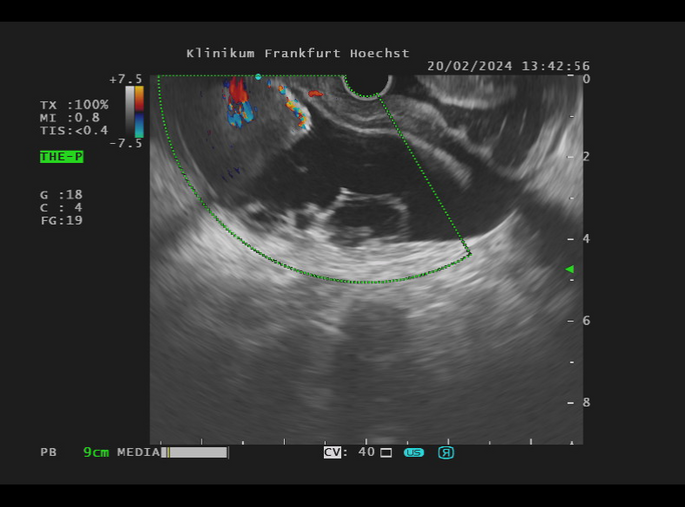

Die Endosonographie ermöglicht eine sehr schonende Diagnostik und Therapie an den Bauchorganen. Im Vergleich zu anderen bildgebenden Verfahren wie der Abdomensonographie, der Computertomographie (CT) oder der Magnetresonanztomographie (MRT) bietet nur die Endosonographie den Blick von innen auf die Organe. Die Speiseröhre (Ösophagus), Magen, Zwölffingerdarm (Duodenum), Bauchspeicheldrüse (Pankreas), Gallenwege, Gallenblase und Enddarm (Rektum) liegen besonders im Fokus der Endosonographie.

Die Untersuchung wird in der Regel unter Sedierung, also mit einer Schlafspritze, durchgeführt, wie man es von der Magen- oder Darmspiegelung her kennt. Wo noch vor wenigen Jahren häufig eine Operation notwendig wurde, kann heute die endosonographische Therapie weiterhelfen. Beispiele hierfür sind die Ableitung von Flüssigkeitsverhalten nach innen und die Abtragung von entzündlichem oder untergegangenem Gewebe (endosonographische Drainage, Pankreatikogastrostomie, Choledochoduodenostomie, endoskopische Nekrosektomie, endosonographische Stenteinlage).

Aber auch bei der Gewinnung von Gewebeproben auf möglichst schonendem Wege kommt die Endosonographie zum Einsatz. Hierbei werden Proben z.B. aus dem Pankreas, Lymphknoten oder anderweitigen Befunden entnommen (endosonographische Punktion, endosonographische Feinnadelaspiration). Neuere Techniken umfassen die Therapie von Gallenblasenentzündungen (endosonographische Gallenblasendrainage)  und die Wiederherstellung der Nahrungspassage bei Verlegungen im Magen-Darm-Trakt (endosonographische Gastroenterostomie).